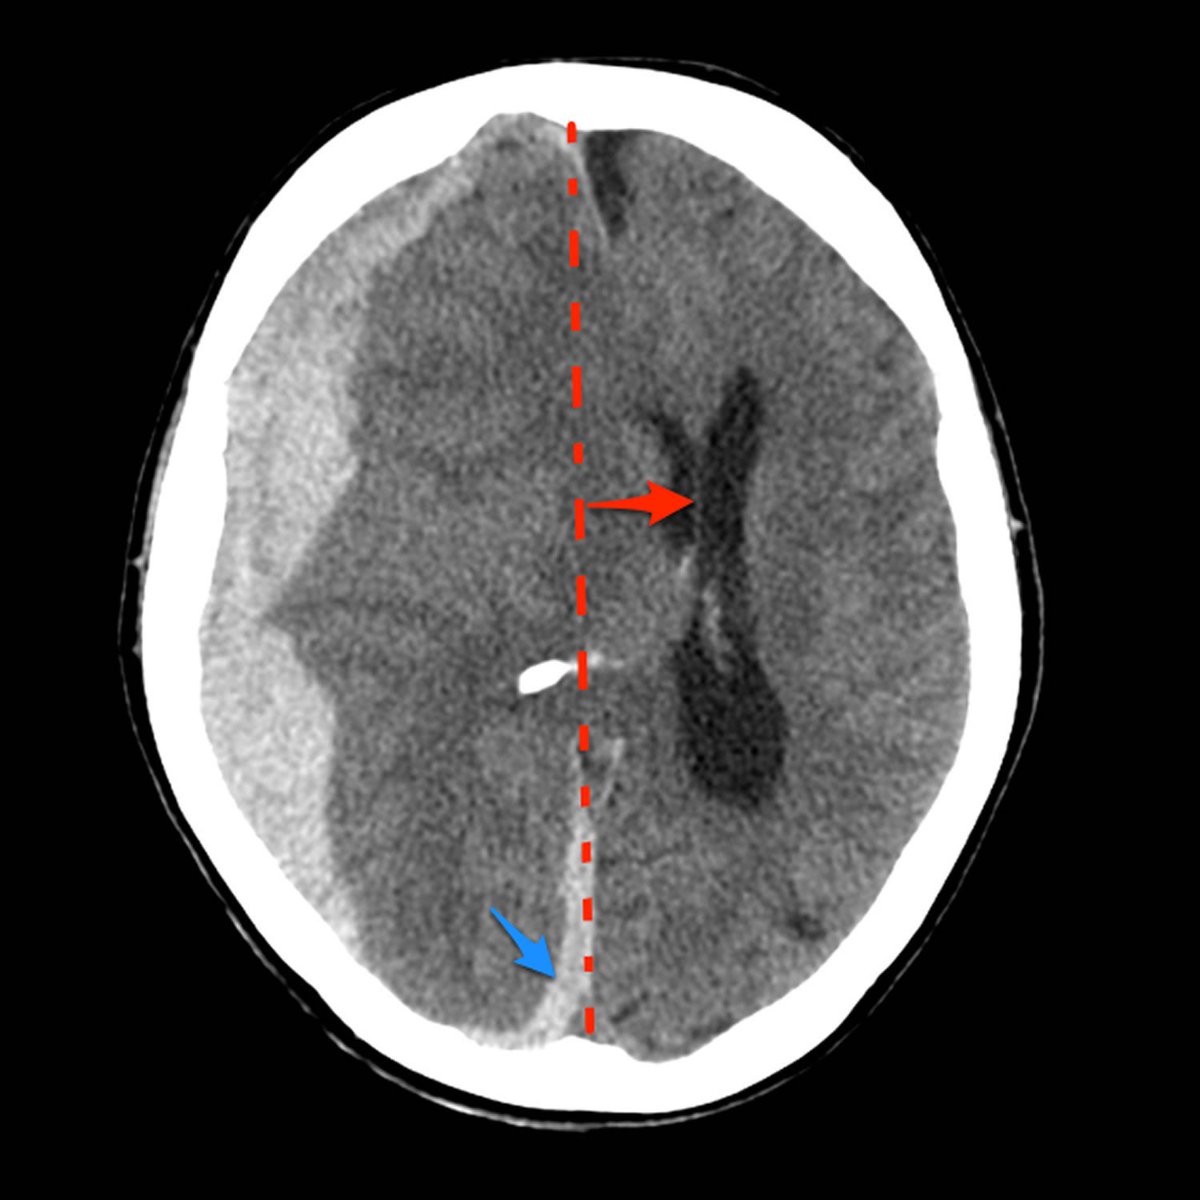

✳️ Midline shift➕herniation

▫️Subdural hematoma🩸🧠

✳️Cresent shape that cross suture lines

✳️Have 3 main types 🌟👇🏻

🛑notice that, the acute commenly have medline shift